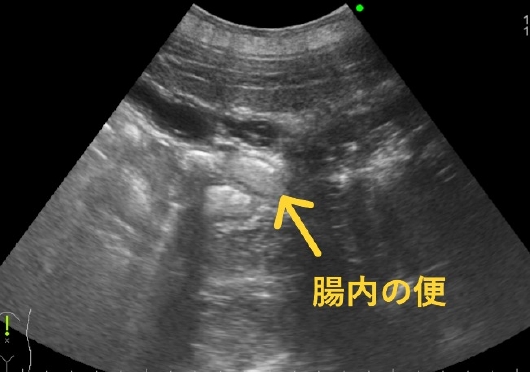

少し見えた腸はしっかりと動いていて、腸内の便がうにょうにょと押し流されていました(笑)